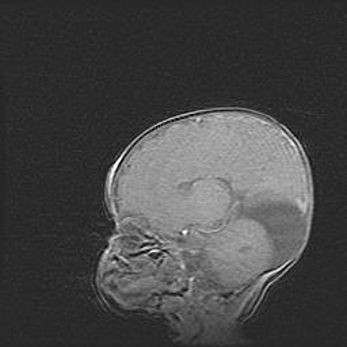

Мальформация Денди-Уокера. Киста задней черепной ямки.

Агенезия мозолистого тела.

Возраст: 2,5 месяца

Вес: 2420 г

Пол: женский

Окружность головы: 37 см

Срок гестации: 32 недели

Мальформация Денди—Уокера — редкий вид патологии ЦНС, представляющий собой врожденный порок развития каудального отдела ствола и червя мозжечка, ведущий к неполному раскрытию срединной (Мажанди) и латеральных (Лушка) апертур IV желудочка мозга. Для этогно синдрома характерна триада симптомов: гипотрофия червя мозжечка и/или полушарий мозжечка, кисты задней черепной ямки, гидроцефалия различной степени. В 70% случаев порок сочетается и с другими аномалиями головного мозга, в частности с агенезией мозолистого тела.